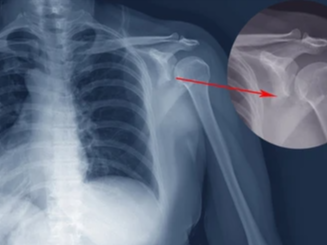

상완골 골절 치료 방법과 수술 여부

상완골 골절은 반드시 수술이 필요한 것은 아니며, 골절 상태에 따라 보존적 치료와 수술적 치료로 나뉩니다.

- 수술 치료

- 금속 핀, 플레이트, 나사 고정

- 골절이 심하거나 어긋난 경우

- 기능 회복을 위해 정렬이 중요한 경우